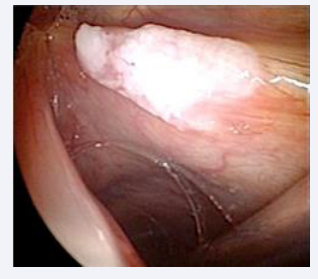

This prevalence is justified due to the surgeon’s special attention during the trans-operative period, and the following aspects were observed: the leukoplakia may be microscopic, it may be located throughout the glottis, especially at the vocal fold level, it may be associated to the initial surgical lesion, it may be contralateral to it, it may be located in the epithelium of this lesion or it may also be subglottic. Intraoperative staging with microscopy, palpation maneuvers and the use of rigid endoscopes angled at 30, 70 and 120 degrees favor the detection of leukoplastic lesions [Figures 2-5].

Leukoplakia with variation in location and quantity

Figure 3: Leukoplakia with variation in location and quantity